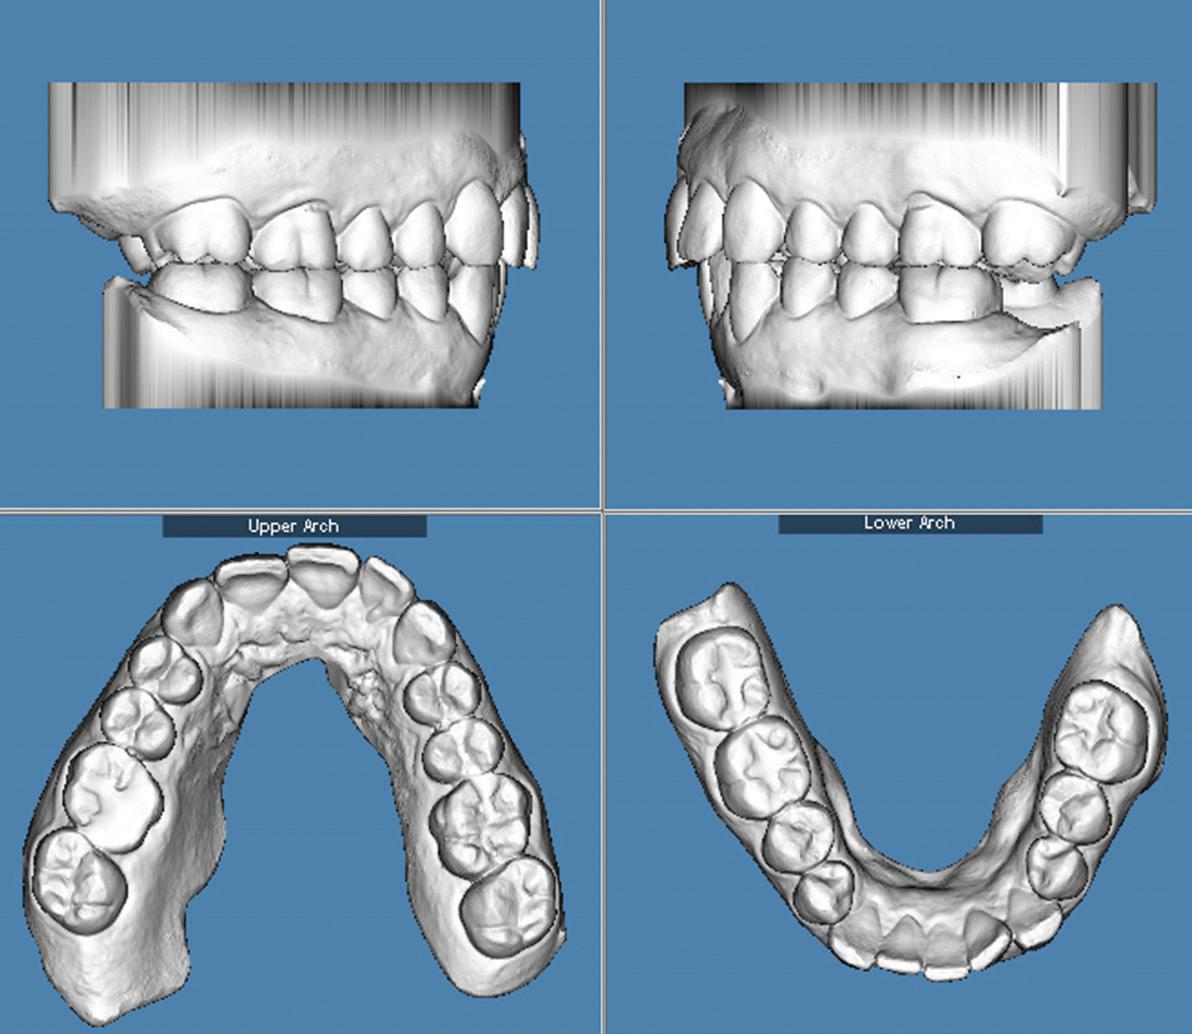

Adilson Yoshio Furuse

2 CE CREDITS, P. 25

Shear bond strength of resin cement to a CAD/CAM millable alloy subjected to various surface treatments

47 Orthodontics

Clear aligner therapy and symptoms of temporomandibular disorders: a case report

Lina Sharab

Bushra Butul

Aqib Shafi

Jeffrey P. Okeson

SELF-INSTRUCTION EXERCISE GD538, 2 CE CREDITS, P. 53